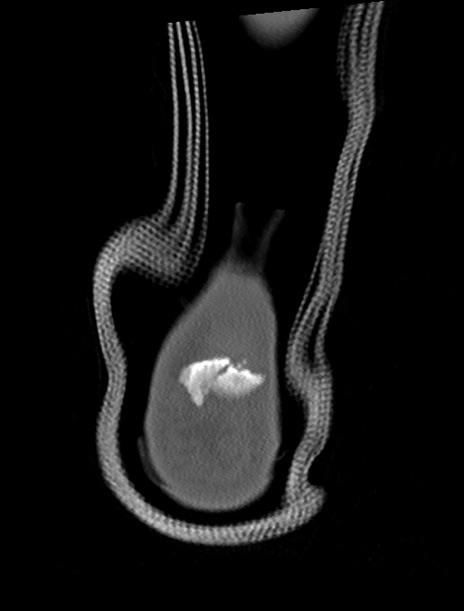

左足関節CT

横断像